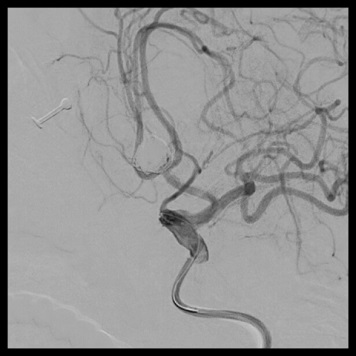

脳動脈瘤内塞栓術

術前

術後